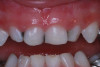

(2.) Lingual and facial maxillary views of 5-year-old patient, 1 year after caries attenuation with SDF. The parents were not concerned about the black staining.

(3.) Lingual and facial maxillary views of 5-year-old patient, 1 year after caries attenuation with SDF. The parents were not concerned about the black staining.